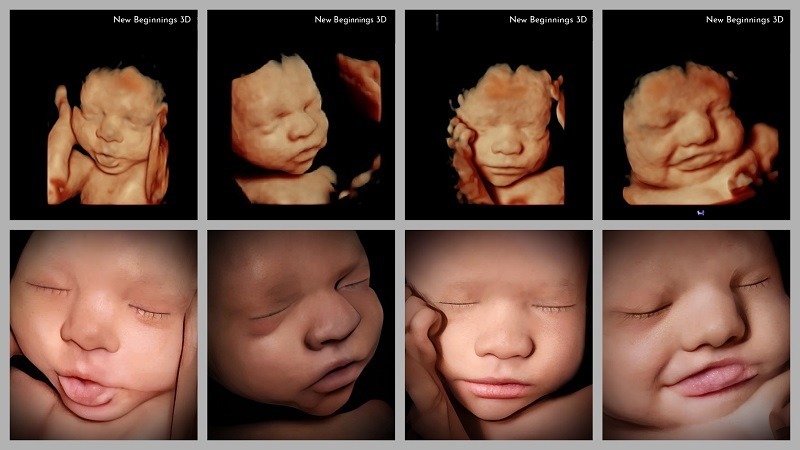

Nên lựa chọn siêu âm 5D

Siêu âm 5D là công nghệ hiện đại nhất hiện nay, mang đến hình ảnh sắc nét, màu da và biểu cảm của bé gần như thật. Phương pháp này thường phù hợp với mẹ bầu muốn lưu giữ hình ảnh thai nhi một cách sống động hoặc khi bác sĩ cần đánh giá kỹ hơn về cấu trúc giải phẫu. So với 4D, siêu âm 5D giúp phát hiện những dị tật nhỏ và khó thấy hơn nhờ độ phân giải cao. Tuy nhiên, chi phí siêu âm 5D thường cao hơn, vì vậy mẹ bầu nên cân nhắc giữa nhu cầu trải nghiệm và mục đích y khoa.